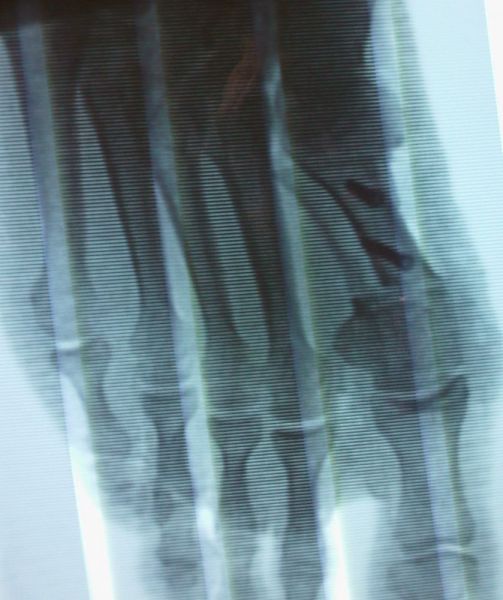

1. Ηallux valgus of the right foot in a 28-year-old female.

Treatment: Scarf osteotomy of the first metatarsal

I. Anteroposterior x-ray foot during procedure shows the scarf osteotomy with two screws II. This image shows the foot in a standing position one year down the line from the procedure. The young lady is very happy.